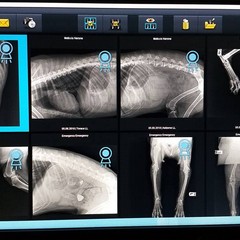

In serata, infatti, Nerone è stato visitato e dalle lastre fortunatamente non sono risultate fratture ma solo escoriazioni sulle zampe posteriori, una più profonda non suturabile per presenza di sporco e peli sottocutanei.